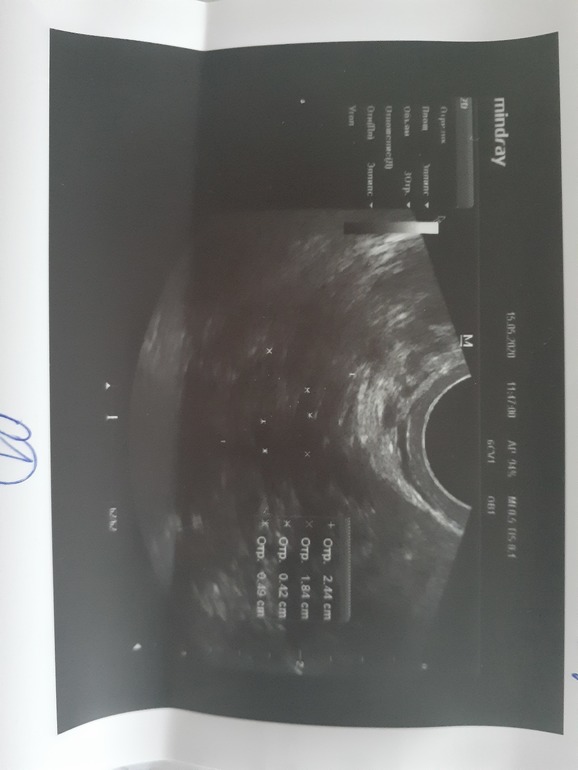

Девочки привет!!! Моя долгожданная беременность наступила и я очень счастлива 🥰 последние месячные 14 апреля, очень тянет низ живота справа, решила сходить на узи исключить вб, понимаю что рано, но очень переживала. По результатам узи в матке плодное яйцо 2.5 мм. Но жт четко не определяется! Сказали прийти через 3 недели повторно. У кого так было что жт не определялось или не было вообще? И благополучно ли завершилась беременность?

А включение в яичнике, либо сама киста ЖТ, либо ЖТ не видно из-за кисты.

Для желточного мешочка еще очень рано. А по поводу тела, скорее всего спряталось за кистой в левом яичнике. Не быть его не может. Поэтому не беспокойтесь и настраивайтесь на положительные эмоции!=)